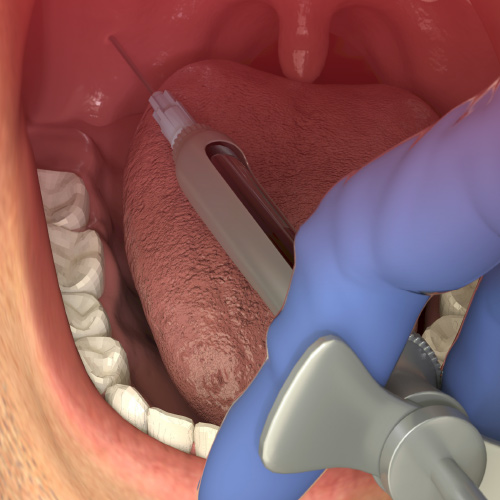

Beyond Injection: Technology for Better Local Anesthesia

Pain and anxiety from anesthetic injections is not inevitable. A more comfortable injection significantly improves patients’ satisfaction with their experience. Patients will remember comfortable anesthesia more than other aspects of the appointment, and are more likely to refer others to the dent...

Painless Local Anesthetic Injections

Tuesday, September 29, 2020

Buffering: the key to more effective and comfortable local anesthesia

This continuing education (CE) article focuses on how buffering of local anesthetics offers significant advantages for the dentist and patient. Buffering local anesthetics to a neutral pH range addresses inconsistencies in anesthetic performance such as speed of onset, depth of anesthesia, comfort o...

Reduce Dental Anxiety and Pain With Computer-Controlled Injection

For most patients, anesthesia delivery is an uncomfortable and anxiety-producing part of the dental appointment. A pain-free experience can be a pleasant surprise that results in more referrals and patient loyalty. Learn how you can deliver a positive and painless session through computer-controlled...

How Buffered Anesthetic is Revolutionizing Dentistry

Explore how recent innovations have made buffering local anesthetics easier and more accessible, benefiting both practitioner and patient.